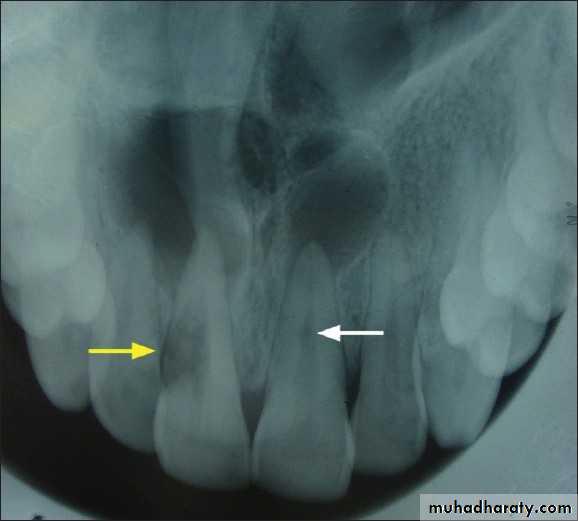

• Radiographic changes:

– Radiolucent enlargement of pulp canal

– Original root canal outline distorted

– Bone changes are seen only when root perforation into periodontal ligament takes place.